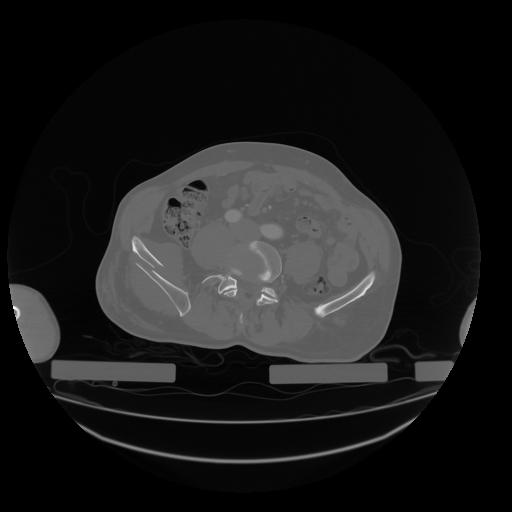

28 CUERPO,CE,Vol,2.0,CUERPO,,